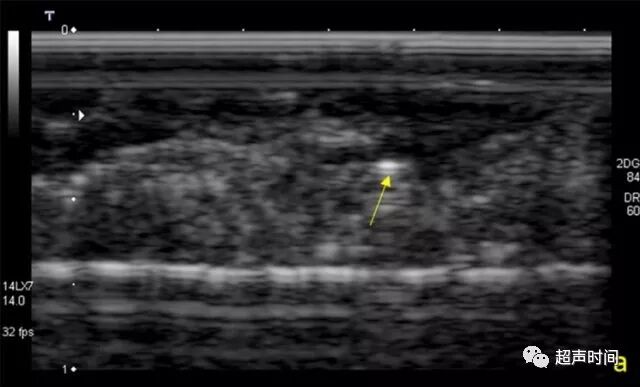

图 1 乳腺术后标本超声图像。图 a 灰阶超声显示一个微钙化灶(箭头);图 b 在 a 中相同区域,MicroPure 显示出数个微钙化灶(箭头)

研究结果显示,所有医师通过 MicroPure 发现微钙化的平均数明显多于灰阶超声,分别为 14.0±12.0 与 3.0±3.2。并且每名医师在 MicroPure 图像观察到的微钙化数均多于灰阶超声图像(图 1)。而钼靶显示的微钙化(平均 27.0±19.2)较灰阶超声或 MicroPure 更多。